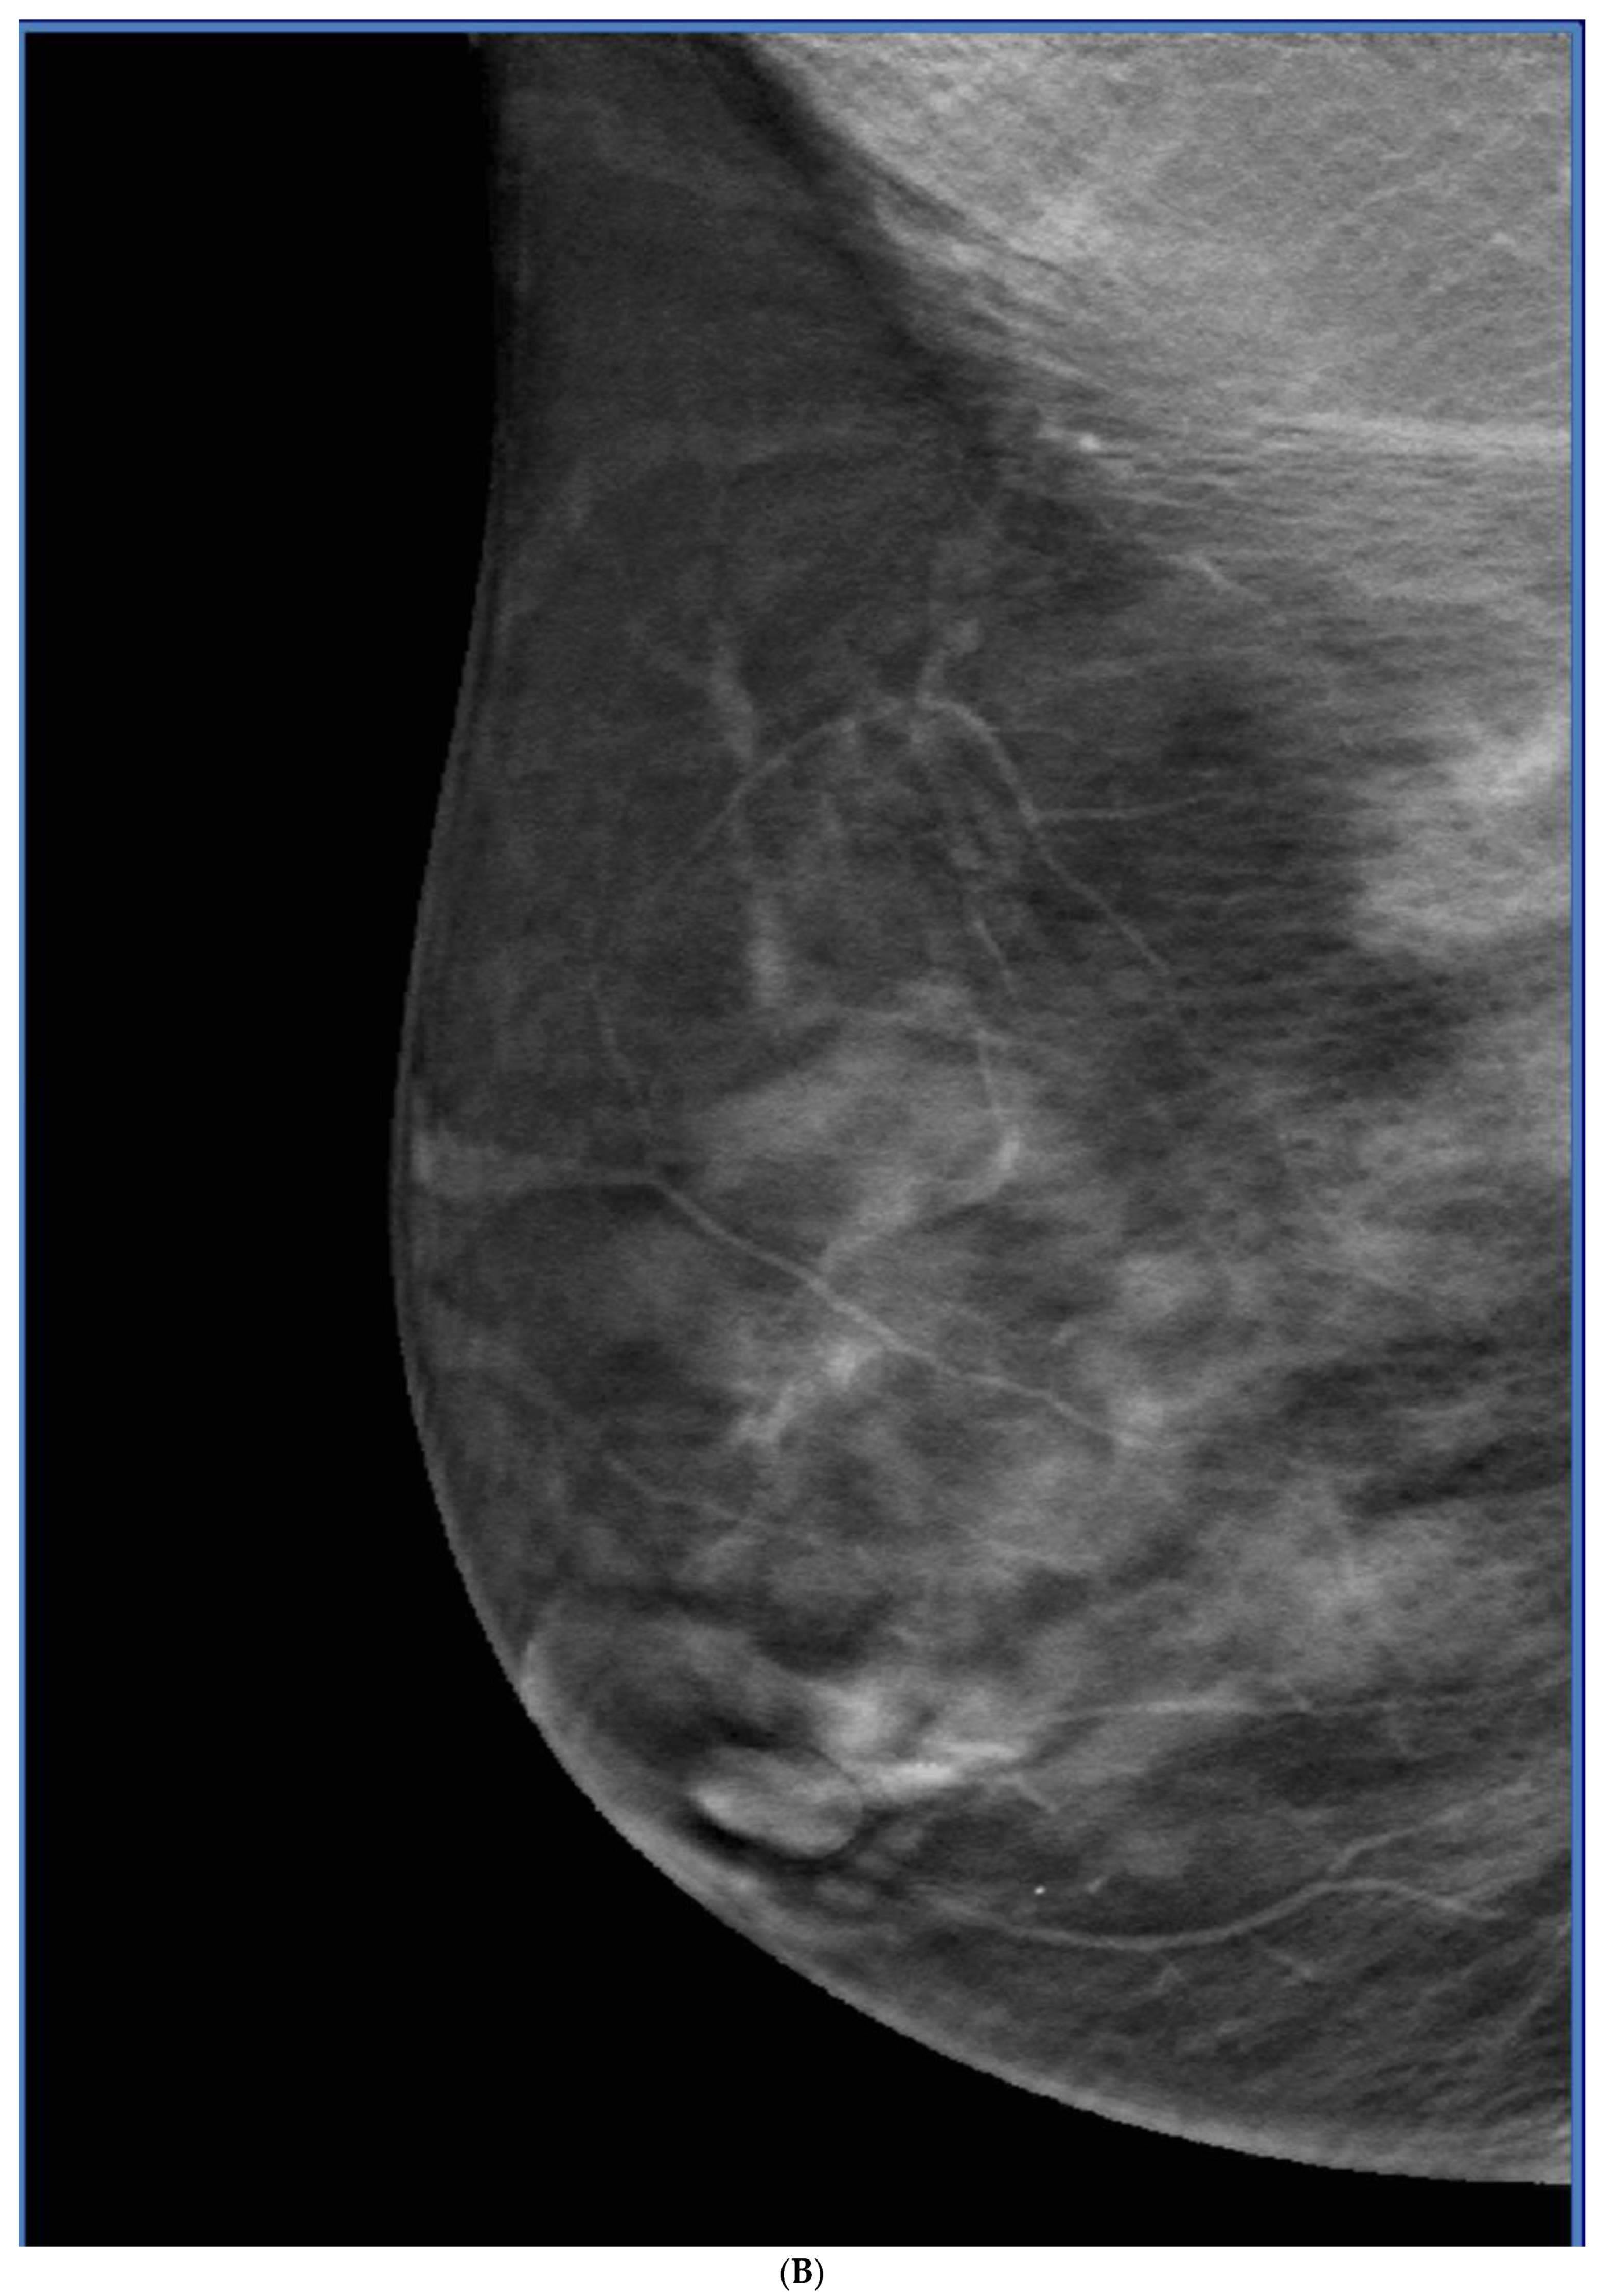

5. Ultrasound (US)